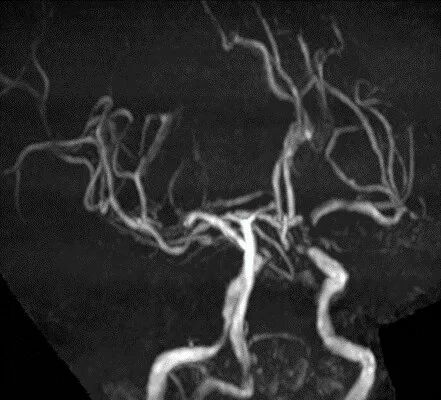

入院影像检查

导丝怎么扩【载药时代 球扩天下】NOVA DES®颅内药物洗脱支架在颈内动脉颅内段重度狭窄中的应用体会二例!_https://www.jmylbn.com_新闻资讯_第20张

导丝怎么扩【载药时代 球扩天下】NOVA DES®颅内药物洗脱支架在颈内动脉颅内段重度狭窄中的应用体会二例!_https://www.jmylbn.com_新闻资讯_第21张

重要影像结论:右侧颈内动脉C4段重度狭窄;右侧颈内动脉C6段中度狭窄;左侧颈内动脉C5段中度狭窄;左侧大脑前动脉A1段重度狭窄。